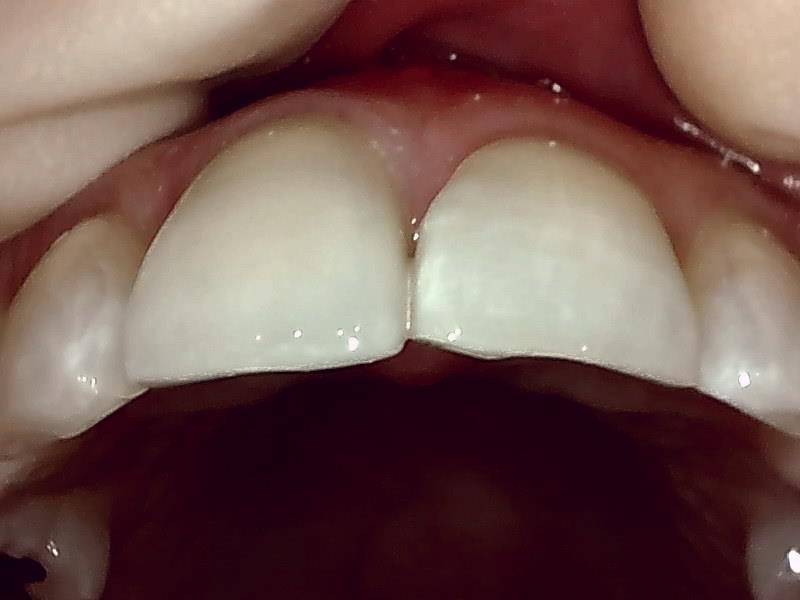

ジルコニアセラミック冠の装着前の支台歯形成(写真)

仮歯の装着して近心歯肉の回復を待つ。

仮歯の装着後、歯肉の治癒期間は後1~2週間後程度になる。